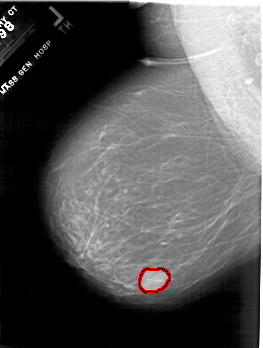

A_1801_1.LEFT_MLO

LEFT_MLO LINES 6601 PIXELS_PER_LINE 4981 BITS_PER_PIXEL 12 RESOLUTION 43.5 OVERLAY

FILE: A_1801_1.LEFT_MLO.OVERLAY

TOTAL_ABNORMALITIES 1

ABNORMALITY 1

LESION_TYPE MASS SHAPE LOBULATED MARGINS CIRCUMSCRIBED

ASSESSMENT 4

SUBTLETY 5

PATHOLOGY BENIGN

TOTAL_OUTLINES 1

BOUNDARY